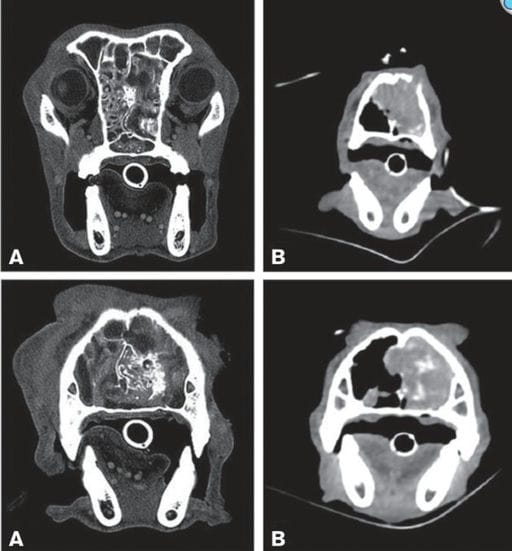

Clinical signs included sneezing (91%), nasal discharge (83%), stertor (74%), and frontonasal deformation (17%). Radiography and CT often revealed turbinate lysis, bone erosion, or radiopacity similar to neoplasia. Endoscopy showed characteristic smooth, pink, elastic polypoid tissue.

Transverse CT images (A — Case 1, B — Case 15) of the bone and soft tissue window. In all images, a mass involving the nasal cavity (A and B left) is clearly visible, characterized by patchy contrast enhancement (B) and destruction of turbinates and parts of the bony nasal septum (A and B). Partial lysis of the nasal bone is also present (B). The mass extends into the choanae and the rostral aspect of the nasopharynx (A).